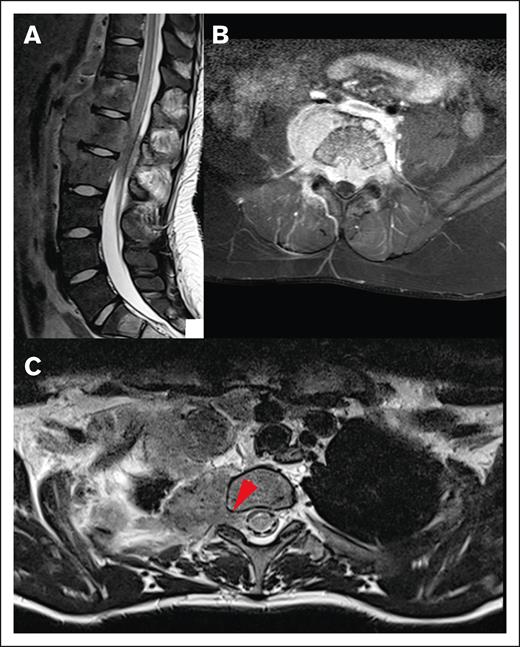

Most lesions (92.7%) extended through the neural foramina of either the vertebrae or sacral bone; 2 lesions did not extend through the neural foramina, and 2 lesions could not be evaluated (Figure 4). Thirty-one lesions entered the spinal canal. Of these, 54.8% caused displacement of the spinal cord, 25.8% were adjacent to the spinal cord but did not cause displacement, and 19.4% did not contact the spinal cord (Figure 5). None of the lesions infiltrated into the spinal cord itself. Spinal cord edema was evaluated for patients who had MRI available (17 of 31 lesions). Among these evaluable lesions, only 12.9% had evidence of spinal cord edema.

Figure 5.

Local impact on CNS structures. (A) Displacement and mild compression of spinal cord to the right without contrast enhancement in the transverse T1 fat saturated image. (B) The same patient with edema clearly visible in the spinal cord in a sagittal T2-weighted MRI image.